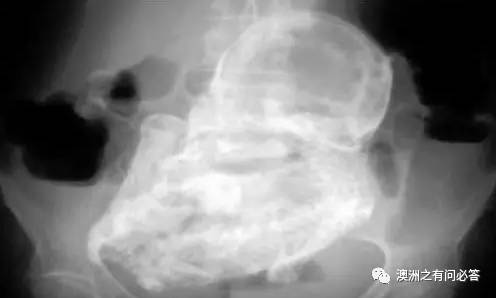

经过进一步的确认,

男孩的腹部的这个肿块,

竟然是一个胎儿...

而且这个胎儿在男孩的肚子里,

竟然还在不停地发育成长,

虽然他的脊椎头骨等位置都已变性,

但他确确实实在成长...